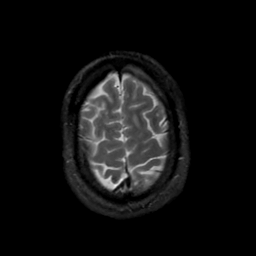

MR Study #17, July 7, 1991 -- Slice #43

[Home][Help][Clinical][Tour 1][Tour 2] Slice 43